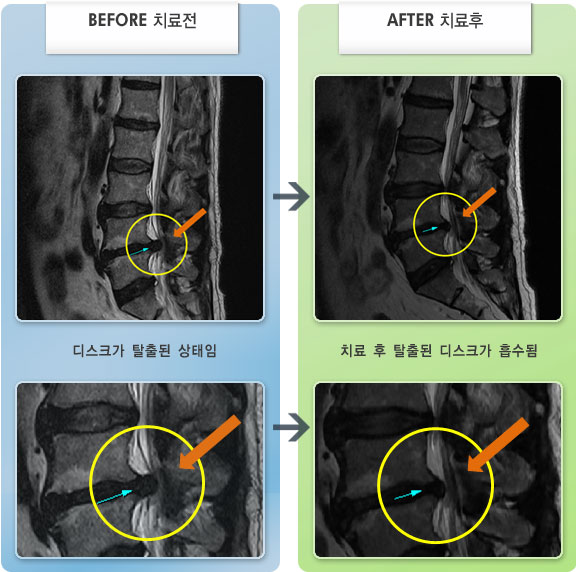

Before

After

허리통증이 심해서 숙이기 어렵고 차에서 내리기 힘들었습니다.

2021.01.06 ~ 2025.03.10